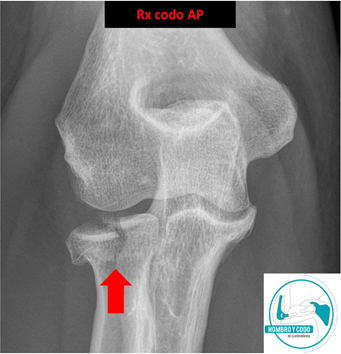

Fractura de la cabeza del radio

(muy común en caídas con el brazo extendido).

Las fracturas de cúpula radial son más comunes en personas jóvenes y activas, pero también pueden afectar a adultos mayores, especialmente aquellos con osteoporosis, como resultado de una caída sobre el brazo extendido o en semiflexión. Es la fractura más común del codo (30% de todas las fracturas del codo), y con mayor prevalencia en mujeres (♂:♀= 2:3).

Su espectro de lesión va desde las fracturas no desplazadas simples, a aquellas más complejas multifragmentarias (o conminutas), o en el contexto de una luxación del codo .